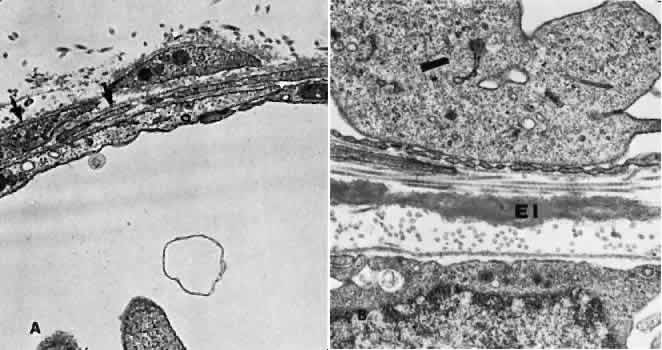

The iris blood vessels derive from the major iridic arterial circle and drain into the vortex system. The blood vessels of the iris are believed to have a slight corkscrew shape so they can accommodate to the changes in the length of the iris during dilation and contraction. A striking finding in all the iris vessels is the presence of thick collagenous adventitia that is several microns thick. There are approximately 200 radial vessels in the iris. The density of these vessels is greater than expected for the nutrition of the iris, and they probably account for anterior-segment thermal homeostasis and provide a high oxygen content for the corneal endothelium. Most of the vessels in the iris stoma are arterioles (Figs. 18, 19, and 20), venules, and capillaries (Fig. 21). The capillaries have unfenestrated endothelium with tight junctions. The main branches of these radial vessels form an incomplete circular arterial ring at the collarette (minor iris circle). Branches from the minor circle extend into the pupillary region to form capillary arcades. The venous drainage system parallels the arterial inflow pattern. The radial arteries of the iris are truly arterioles, with an overall diameter of 15 to 50 μm. The radial iridial veins are technically pericytic venules. They are approximately 30 to 90 μm in diameter. The media consists of one or two layers of pericytes. These cells make frequent contact with the endothelial cells but not with each other.

Fig. 18. Electron micrograph of a human iridial arteriole. The endothelial cell (E) is richly supplied with cellular organelles. In some areas (arrow), the smooth muscle cells (S) are in close contact with the endothelial cells.

Fig. 19. Electron micrograph of a human iridial arteriole from an older patient. Debris may be seen in the basement membrane surrounding the smooth muscle cells (arrows).

Fig. 20. Electron micrograph of a precapillary arteriole from a human iris in the region of the constrictor muscle. An incomplete layer of smooth muscle cells containing dense bodies (arrows) is present.